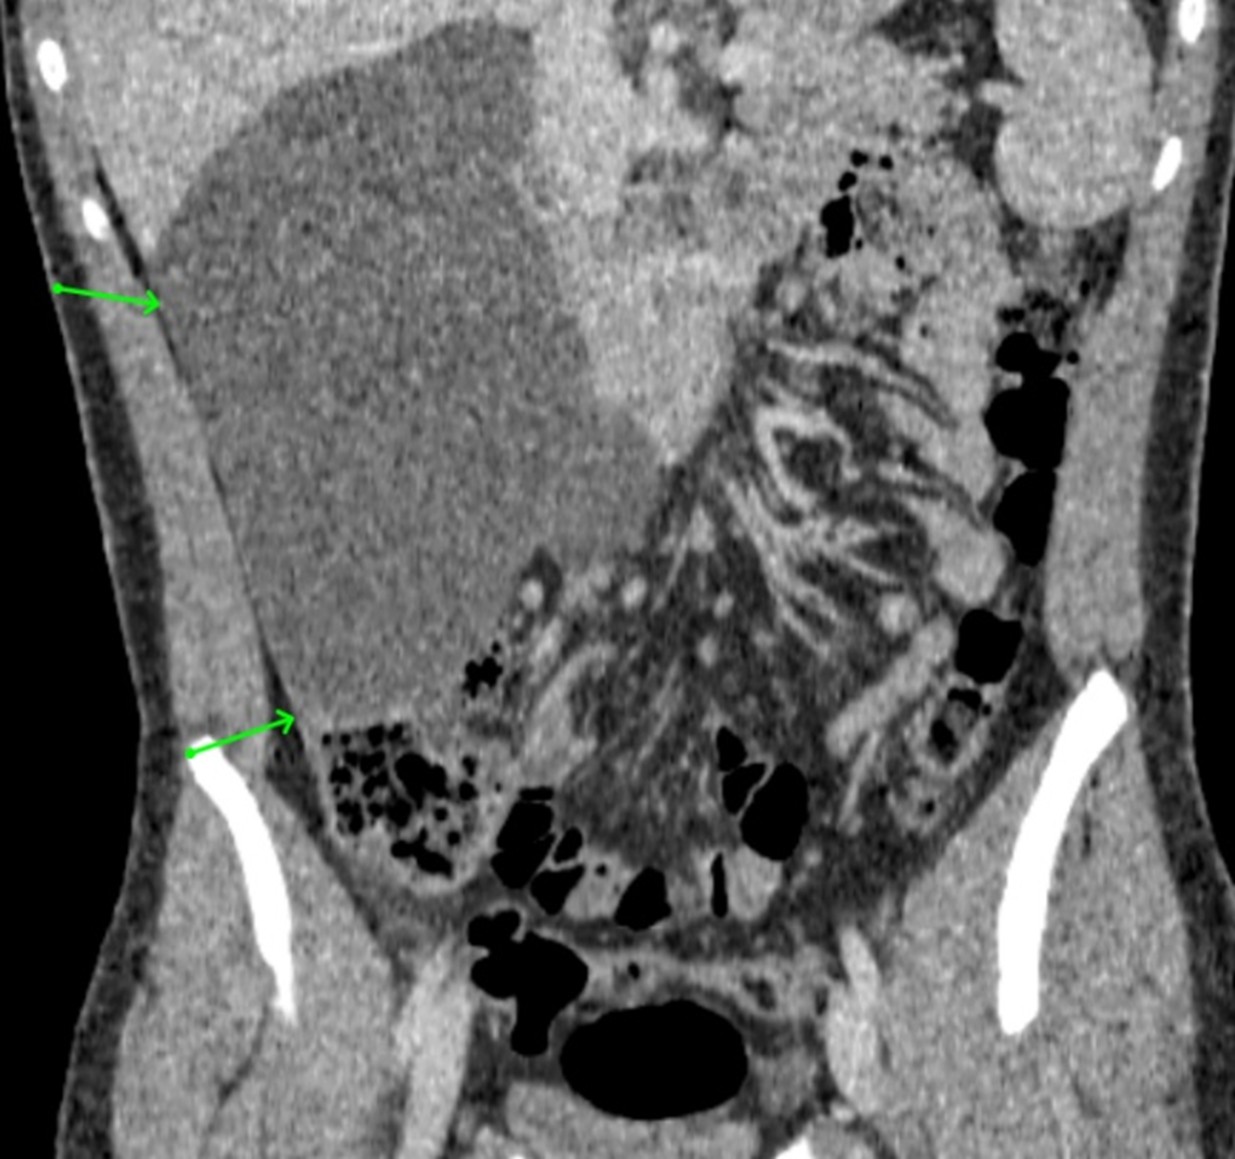

Malignant Rhabdoid Tumor of the Kidney in an 11-Month-Old Child: Case Report and Literature Review

Laura Mendes Lopes, Fabricio Grenteski, Carlos Roberto Naufel Júnior , Guilherme Andrade Coelho, Guilherme Ferrarini Furlan, Nertan Tefilli, José Anderson Feitoza , Igor Luna Peixoto